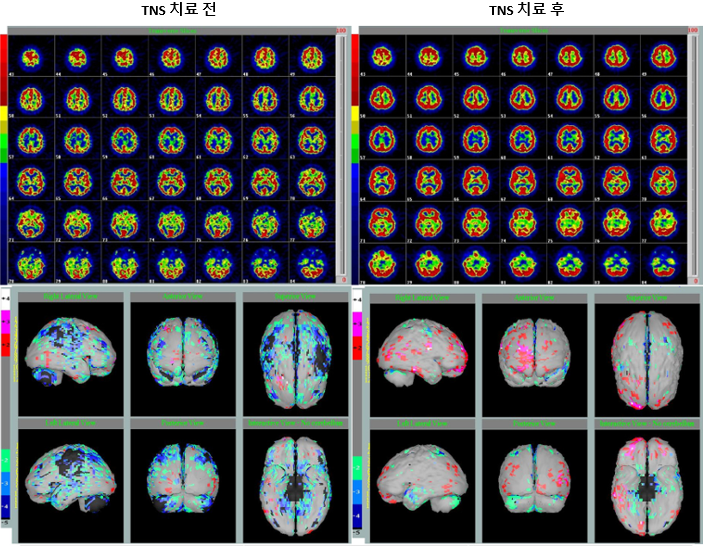

관련 연구에서는, DRE 환자 10명을 대상으로 TNS 자극 전후의 뇌 혈류 변화를 평가하기 위해 SPECT 검사를 시행하였습니다.

자극은 양측 안와하신경(infraorbital nerve)에 20분간 적용되었고, 펄스폭 0.25 μs, 주파수 120 Hz 자극 파라미터가 사용되었습니다. 자극 강도는 각 환자가 불편함 없이 견딜 수 있는 최대 수준으로 설정되었습니다. (대부분 6-12 mA 범위)

기저선(baseline) SPECT 영상에서는, 모든 환자에게서 국소 또는 전반적인 뇌 저관류(cerebral hypoperfusion)가 관찰되었습니다.

하지만 TNS 자극 후에는 70% 환자에서 저관류 점수가 감소함과 동시에, 피질 전반에서 추적자 섭취(tracer uptake)가 증가하는 양상이 나타났습니다 [그림 8].

특히 Odd ratio 정량 분석 결과, 측두엽(temporal lobe)과 번연계(limbic lobe)에서 혈류가 증가한 환자의 비율이 유의하게 높은 것으로 나타났습니다.

주목할 점은, TNS 이후 혈류 회복이 관찰된 부위가 대부분 환자들의 실제 뇌전증 병소와 일치했다는 사실입니다.

즉, 예를 들어 측두엽에 병소가 있는 DRE 환자들은 측두엽에서 저관류가 관찰되었고, TNS 자극 후에는 그 측두엽 부위에서 혈류가 회복되는 양상을 보였다..라는 맥락으로 이해하시면 좋겠습니다.

이러한 결과는, TNS가 피질(cortical)-피질하(subcortical) 구조를 포함한 뇌전증 네트워크(epileptic network)를 기능적으로 조절 할 수 있음을 시사합니다.

그러니까, TNS는 뇌간(brainstem)에서 대뇌피질(forebrain)까지 이어지는 해부학적·기능적 연결성을 바탕으로,

광범위한 뇌 네트워크에 영향을 주며 항뇌전증 효과(anti-epileptic effect)를 나타낼 수 있다는 가능성을 보여준 연구라고 할 수 있겠습니다.

그림 8. TNS 전후 DRE 환자의 뇌기능 변화.

빨간색은 관류 증가(hyperperfusion), 파란색은 관류 감소(hypoperfusion)를 의미함.